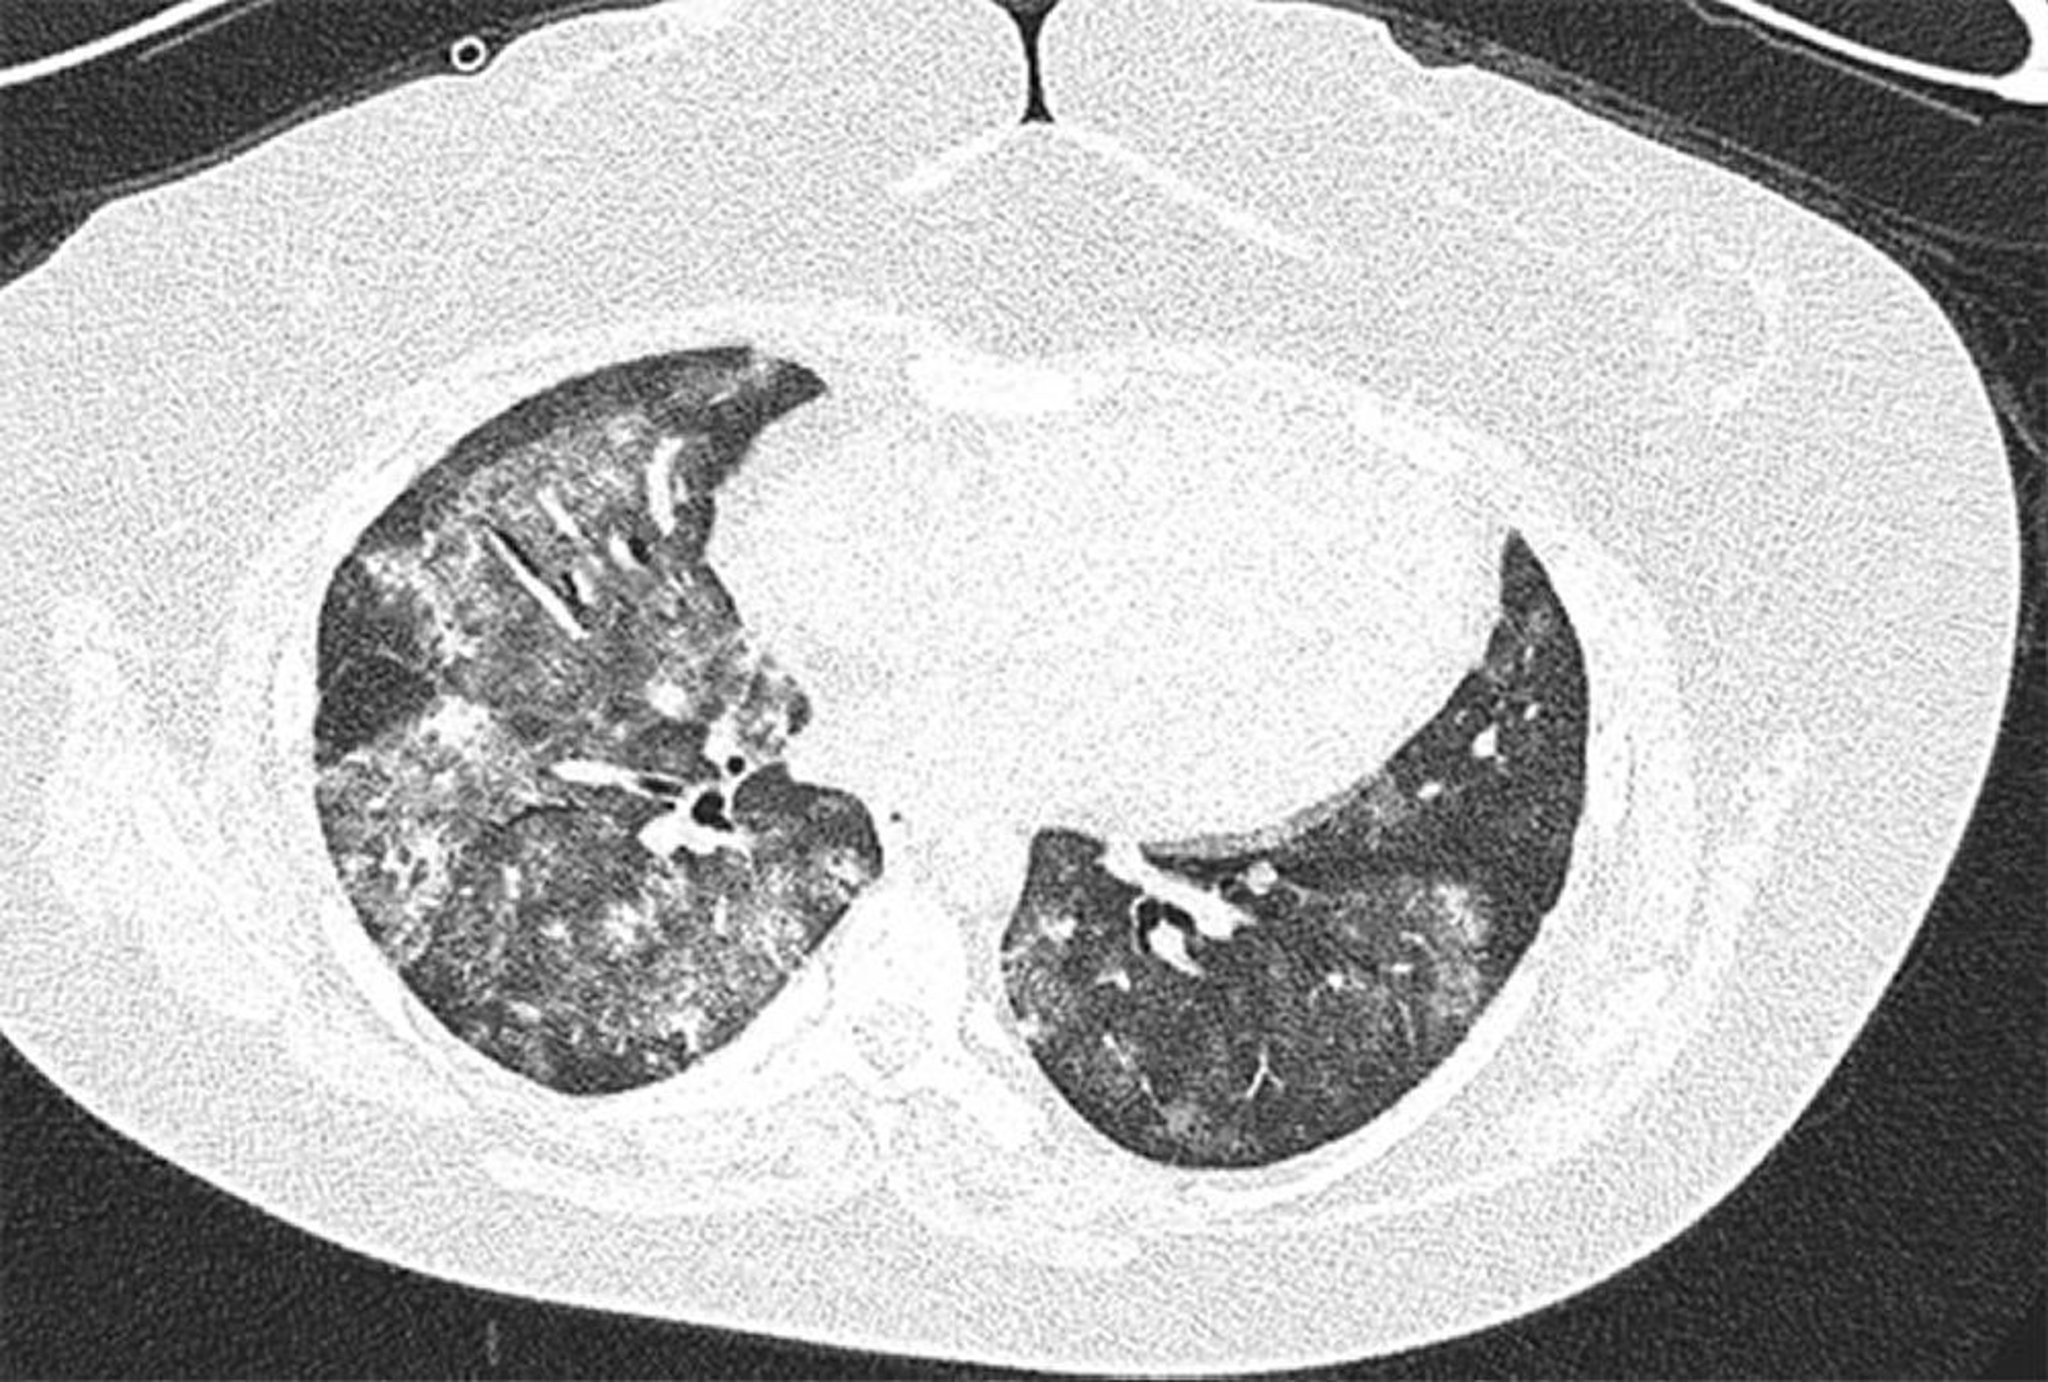

Xuất huyết phế nang lan tỏa

Hình ảnh CT độ phân giải cao của phụ nữ 28 tuổi mắc hội chứng kháng phospholipid với xuất huyết phế nang lan tỏa tái phát. Hình ảnh cho thấy hình ảnh kính mờ ở phế nang hai bên và loang lổ kèm theo không tổn thương dưới màng phổi. Rửa phế quản phế nang xác nhận có xuất huyết phế nang.

Hình ảnh do bác sĩ Joyce Lee cung cấp.